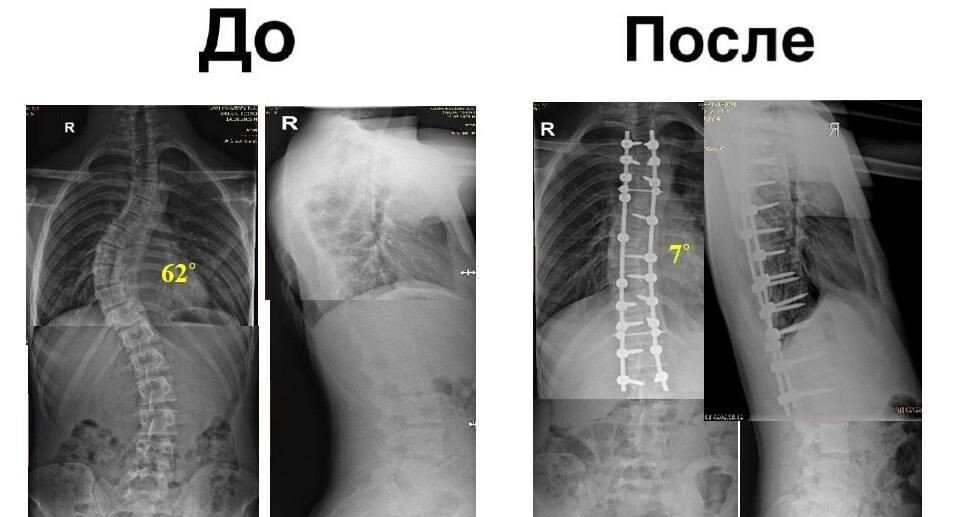

С диспластическим сколиозом грудопоясничного отдела четвертой степени в учреждение поступил 17-летний юноша. Угол деформации достигал 62 градусов, что вызывало выраженный реберный горб и создавало риск сбоев в работе внутренних органов.

Заместитель председателя правительства Московской области – министр здравоохранения региона Максим Забелин пояснил, что хирурги провели сложнейшую операцию: позвоночник выпрямили, придали ему анатомически правильное положение и зафиксировали металлической конструкцией.

Угол искривления удалось уменьшить до семи градусов. Молодой человек избавился от боли, после чего его выписали. Полная реабилитация позволит ему жить без ограничений.